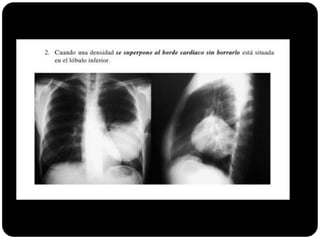

Sinal da silhueta

Lobo médio: borra o contorno direito do coração.

Língula: borra o contorno esquerdo do coração.

Segmentos basais: borram o contorno do diafragma*** (olhar

imagens anteriores para ver quais).

Em que lobo está essa lesão?

Resposta: LID

Importância do

perfil;

Importância da

ausência do sinal da

silhueta;